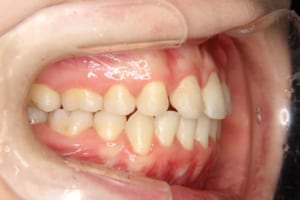

治療後

治療期間 4年6か月

抜歯および非抜歯 上顎:右側中切歯、右側側切歯、左側第一小臼歯

下顎:両側第一小臼歯

顎間ゴムも頑張ってくれたが期間がかかりました。

いずれ牽引した犬歯の再度の補綴処置を予定しています。